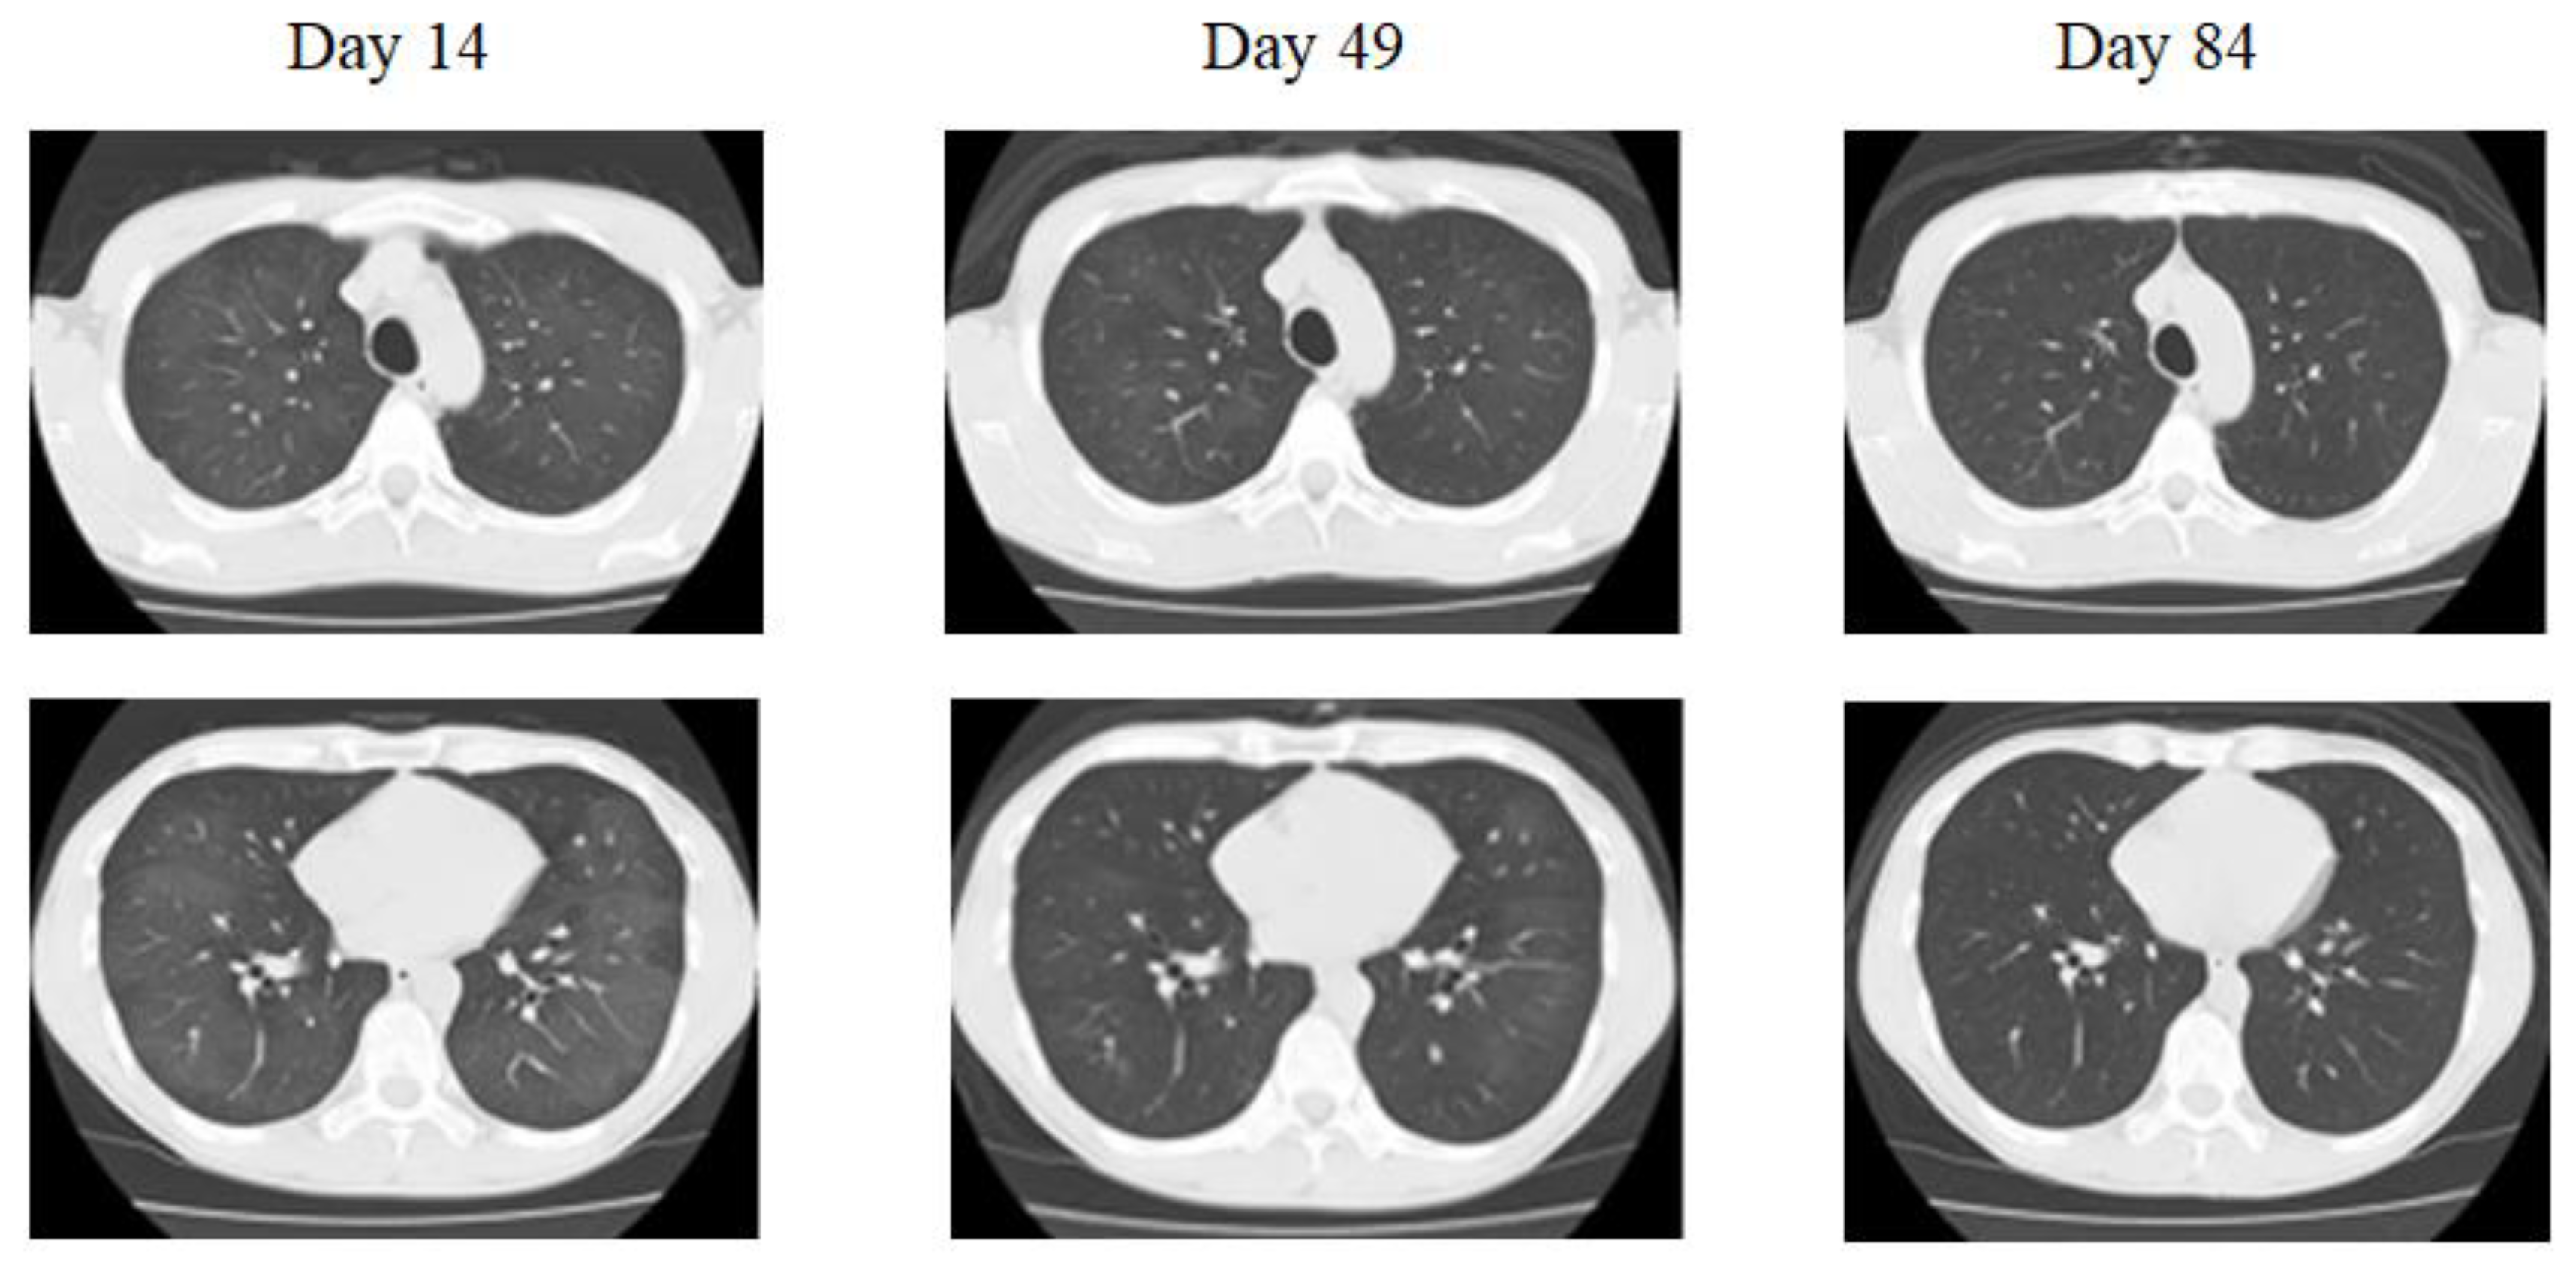

Figure 1.

Chest X-ray and chest computed tomography (CT) in case 1. Bilateral diffuse, ground-glass opacity can be observed, but no pleural nadir shadow. A mosaic pattern can be observed in some areas (Day 14). There is a trend toward shadow reduction in both the upper and lower lung fields, but shadows are still present (Day 49). Improved completely (Day 84).

He had a 28-pack-year history of cigarette smoking for 28 years. He did not take steroids. The light cough persisted and the chest CT performed approximately two months after the onset revealed a residual ground-glass appearance (Figure 1). Finally, three months later, the ground-glass appearance had cleared on the chest CT (Figure 1).